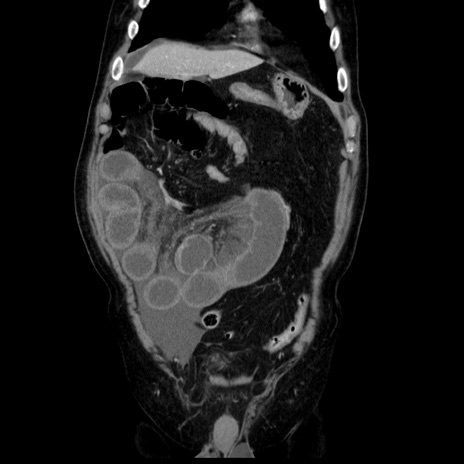

症例30(冠状断像)

【症例】80歳代男性

【主訴】臍周囲痛

【現病歴】約6時間前から臍下部痛が出現。次第に腹部膨隆・背部痛も生じてきたため来院。背部痛の場所は変化しない。

【既往歴】腎盂腎炎

【身体所見】意識清明、BT 36.3℃、BP  131/87mmHg、P 87bpm、SpO2 100%(RA)、臍周囲自発痛・圧痛あり、反跳痛なし、自発痛部位に一致して板状硬あり、腹部膨隆、腸雑音減弱、CVA tenderness両側陰性。

【データ】WBC 19600、CRP 0.33